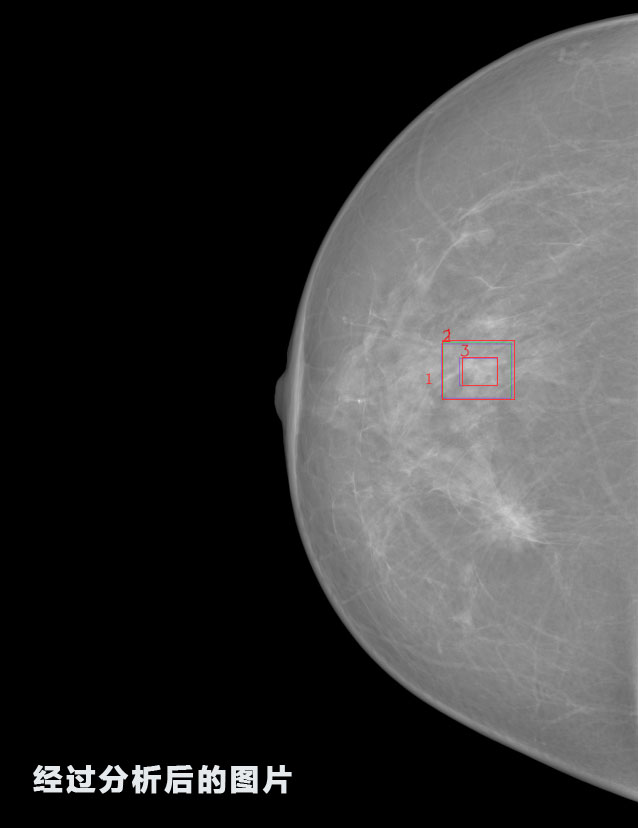

英特健康A(chǔ)I深度學(xué)習(xí)醫(yī)療圖像識別系統(tǒng)案例_乳腺

02.jpg

識別報告:

1.發(fā)現(xiàn)良性鈣化,可能性為19.88%---位置框指數(shù):[1796.0867 1359.8237 2058.1372 1582.5334]

2.發(fā)現(xiàn)惡意鈣化的可能性為15.18%---位置框指數(shù):[1789.4733 1365.9951 2063.7698 1576.0613]

3.發(fā)現(xiàn)惡意鈣化的可能性為12.45%---位于框指數(shù):[1859.3987 1422.3184 2006.5494 1528.2698]